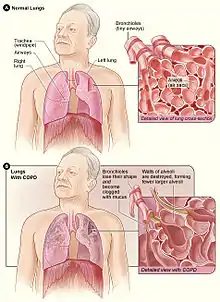

Chronic obstructive pulmonary disease (COPD) is a type of progressive lung disease characterized by long-term respiratory symptoms and airflow limitation.[8] The main symptoms of COPD include shortness of breath and a cough, which may or may not produce mucus.[4] COPD progressively worsens, with everyday activities such as walking or dressing becoming difficult.[3] While COPD is incurable, it is preventable and treatable. The two most common types of COPD are emphysema and chronic bronchitis and have been the two classic COPD phenotypes. However, this basic dogma has been challenged as varying degrees of co-existing emphysema, chronic bronchitis, and potentially significant vascular diseases have all been acknowledged in those with COPD, giving rise to the classification of other phenotypes or subtypes.[9] Emphysema is defined as enlarged airspaces (alveoli) whose walls have broken down resulting in permanent damage to the lung tissue. Chronic bronchitis is defined as a productive cough that is present for at least three months each year for two years. Both of these conditions can exist without airflow limitation when they are not classed as COPD. Emphysema is just one of the structural abnormalities that can limit airflow and can exist without airflow limitation in a significant number of people.[10][11] Chronic bronchitis does not always result in airflow limitation but in young adults with chronic bronchitis who smoke, the risk of developing COPD is high.[12] Many definitions of COPD in the past included emphysema and chronic bronchitis, but these have never been included in GOLD report definitions.[8] Emphysema and chronic bronchitis remain the predominant phenotypes of COPD but there is often overlap between them and a number of other phenotypes have also been described.[9][13] COPD and asthma may coexist and converge in some individuals.[14] COPD is associated with low-grade systemic inflammation.[15]

Definition

Pathophysiology

COPD is a progressive lung disease in which chronic, incompletely reversible poor airflow (airflow limitation) and an inability to breathe out fully (air trapping) exist.[90] The poor airflow is the result of small airways disease and emphysema (the breakdown of lung tissue).[91] The relative contributions of these two factors vary between people.[8] Air trapping precedes lung hyperinflation.[92]

COPD develops as a significant and chronic inflammatory response to inhaled irritants which ultimately leads to bronchial and alveolar remodelling in the lung known as small airways disease.[93][94] Thus, airway remodelling with narrowing of peripheral airway and emphysema are responsible for the alteration of lung function.[55] Mucociliary clearance is particularly altered with a dysregulation of cilia and mucus production.[95] Small airway disease sometimes called chronic bronchiolitis, appears to be the precursor for the development of emphysema.[96] The inflammatory cells involved include neutrophils and macrophages, two types of white blood cells. Those who smoke additionally have cytotoxic T cell involvement and some people with COPD have eosinophil involvement similar to that in asthma. Part of this cell response is brought on by inflammatory mediators such as chemotactic factors. Other processes involved with lung damage include oxidative stress produced by high concentrations of free radicals in tobacco smoke and released by inflammatory cells and breakdown of the connective tissue of the lungs by proteases (particularly elastase) that are insufficiently inhibited by protease inhibitors. The destruction of the connective tissue of the lungs leads to emphysema, which then contributes to the poor airflow and finally, poor absorption and release of respiratory gases. General muscle wasting that often occurs in COPD may be partly due to inflammatory mediators released by the lungs into the blood.[12]

Narrowing of the airways occurs due to inflammation and subsequent scarring within them. This contributes to the inability to breathe out fully. The greatest reduction in air flow occurs when breathing out, as the pressure in the chest is compressing the airways at this time.[97] This can result in more air from the previous breath remaining within the lungs when the next breath is started, resulting in an increase in the total volume of air in the lungs at any given time, a process called air trapping which is closely followed by hyperinflation.[97][98][92] Hyperinflation from exercise is linked to shortness of breath in COPD, as breathing in is less comfortable when the lungs are already partly filled.[99] Hyperinflation may also worsen during an exacerbation.[100] There may also be a degree of airway hyperresponsiveness to irritants similar to those found in asthma.[87]

Low oxygen levels and eventually, high carbon dioxide levels in the blood, can occur from poor gas exchange due to decreased ventilation from airway obstruction, hyperinflation and a reduced desire to breathe.[12] During exacerbations, airway inflammation is also increased, resulting in increased hyperinflation, reduced expiratory airflow and worsening of gas transfer. This can lead to low blood oxygen levels which if present for a prolonged period, can result in narrowing of the arteries in the lungs, while emphysema leads to the breakdown of capillaries in the lungs. Both of these conditions may result in pulmonary heart disease also classically known as cor pulmonale.[46]